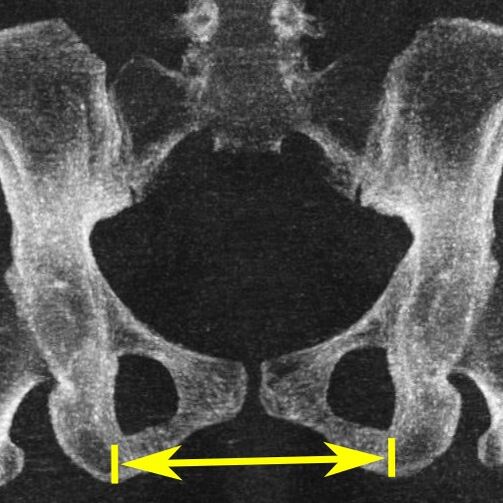

- Поперечный диаметр нижней апертуры — между седалищными буграми — 10,8 (8,1) см

- Distantia intertrochanterica — между большими вертелами бедренных костей — 28-29 см